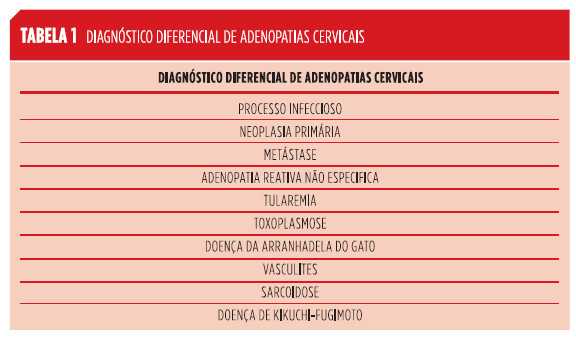

Adenopatias cervicais são um sinal clínico relativamente comum que pode corresponder a uma série de patologias que requerem uma abordagem diagnóstica e terapêutica completamente distintas.12 O diagnóstico diferencial é extenso (Tabela 1).12,13